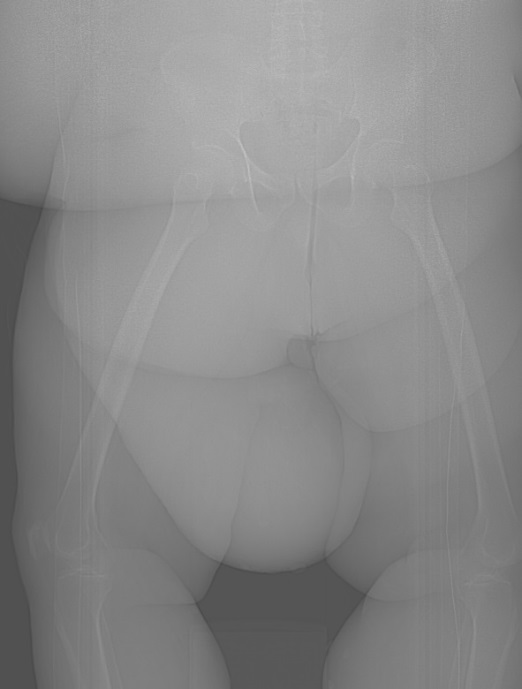

The general surgeon requested enhanced computed tomography (CT) scan (Figure 1 and Figure 2) for the patient as an initial imaging investigation to characterize the nature of the mass. It demonstrated the presence of large mass of fat attenuation in the supero-medial aspect of the right thigh. There is marked skin thickening overlying the mass, involving the anterior abdominal wall as well as bilateral lower thighs. The patient reported history of previous visit to the emergency department two years back with a complaint of left foot pain and swelling. Radiograph was performed at that time (Figure 3) and showed diffuse thickening of the heel-fat pad. Based on the features demonstrated in CT and foot radiograph, the differential diagnosis of massive localized lymphedema (MLL) or atypical lipoma lesion was given.